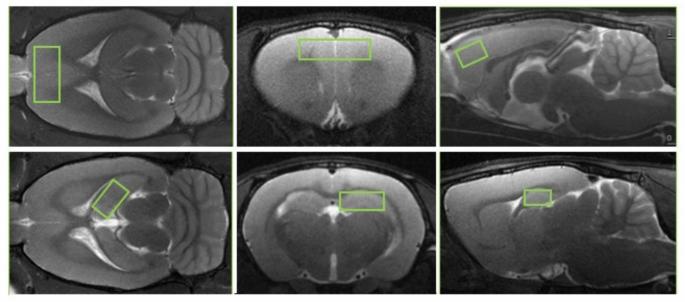

Magnetic resonance spectra were collected from 2 key regions implicated in MDD: the PFC and the Hip, as shown in Fig. 6. Because of the differences in the shape of cortical and subcortical brain areas between WKY and W strains, voxel sizes were slightly adjusted to cover the same functional regions (see details in the figure legend). Multi-slice multi-echo T2-weighted MRI (TR/TE = 2476/7.5 (× 14) ms, matrix 128 × 128, FOV = 25 × 25 mm2, 2 averages) were acquired to measure water T2 for metabolite quantification.

Positioning of the voxels for MRS. Coronal, axial, and sagittal T2W MRI (TR/TE = 2500/33 ms) indicating the voxel positioned in the PFC (upper row; voxel size 6 × 3 × 1.8 = 32.4 mm3 and 6 × 2.85 × 1.8 = 30.8 mm3 in W/CTRL and WKY/CMS brains respectively) and in the right Hip (lower row; voxel size 3.8 × 2.5 × 1.8 = 17.1 mm3 and 3.8 × 2.37 × 1.71 = 15.4 mm3 in W/CTRL and WKY/CMS brains respectively).